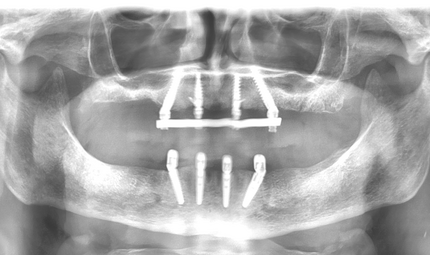

In den letzten Jahren ist eine Zunahme des Interesses an Knochenaugmentationen mit nicht erhaltungs- würdigen Zähnen erkennbar. Das Verwerfen von extrahierten Zähnen ist zurzeit noch tägliche Routine in Zahnarztpraxen und Kliniken. Dieser Fallbericht illustriert die Situation eines 62-jährigen Patienten, bei dem nach Entfernung der Oberkieferfrontzähne der Alveolarfortsatz einen komplexen knöchernen Defekt aufwies. Die Schaltlücke wurde zweizeitig rekonstruiert. Hierbei wurde der knöcherne Defekt mittels der Tooth Shell Technique nach Korsch unter Verwendung von autologem Dentin rekonstruiert und mit zwei Implantaten sowie Implantatkronen prothetisch versorgt. Abschließend erfolgte eine Transplantation von freier keratini-sierter Schleimhaut zur Rekonstruktion des Vestibulums und zur Stabilisierung der periimplantären Mukosa.

In der März-Ausgabe 2022 der Fachzeitschrift Quintessenz Zahnmedizin ist ein fachlich facettenreicher, wissenschaftlich geschriebener Fallbericht erschienen. Die Autoren beleuchten das Thema des vergrößerten Zungenkörpers (Makroglossie). Gelöst wurde dieser besondere Fall in unserer Poliklinik und Abteilung Oralchirurgie im Unterkiefer durch das implantatprothetische Versorgungskonzept All-on-4 und im Oberkiefer kam die bewährte Technik der gaumenfreien Gerüstkonstruktion bei der Doppelkronentechnik zur Anwendung.